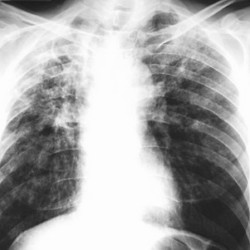

Profilaktyka gruźlicy to przede wszystkim zdrowy tryb życia, higiena kaszlu, szczepienia BCG, leczenie pacjentów zakażonych prątkiem. I oczywiście, co zawarte jest w Narodowym Programie Zwalczania Gruźlicy, wczesna wykrywalność i skuteczne leczenie . – Diagnostyka gruźlicy to rentgen klatki piersiowej, odczyn tuberkulinowy, badania plwociny, bądź wydzieliny oskrzelowej i wyhodowanie prątka z materiałów biologicznych – mówi Joanna Siudzińska, lekarz, specjalista chorób wewnętrznych i specjalista chorób płuc. – Z kolei leczenie polega na skojarzonej terapii antybiotykowej, która by być skuteczna, musi być regularna i trwać minimum pół roku.